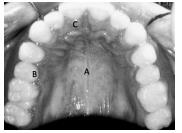

Considerando a imagem apresentada acima, julgue o item subsecutivo.

A letra C indica a gengiva, uma mucosa de revestimento que envolve exclusivamente o colo dos dentes decíduos.